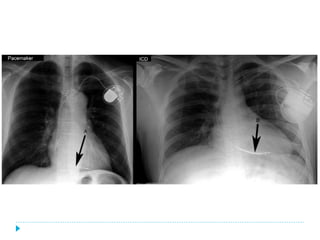

Marcapasos definitivos

Ø Unicamerales

Ø Bicamerales

Ø Tricamerales

(CRT)